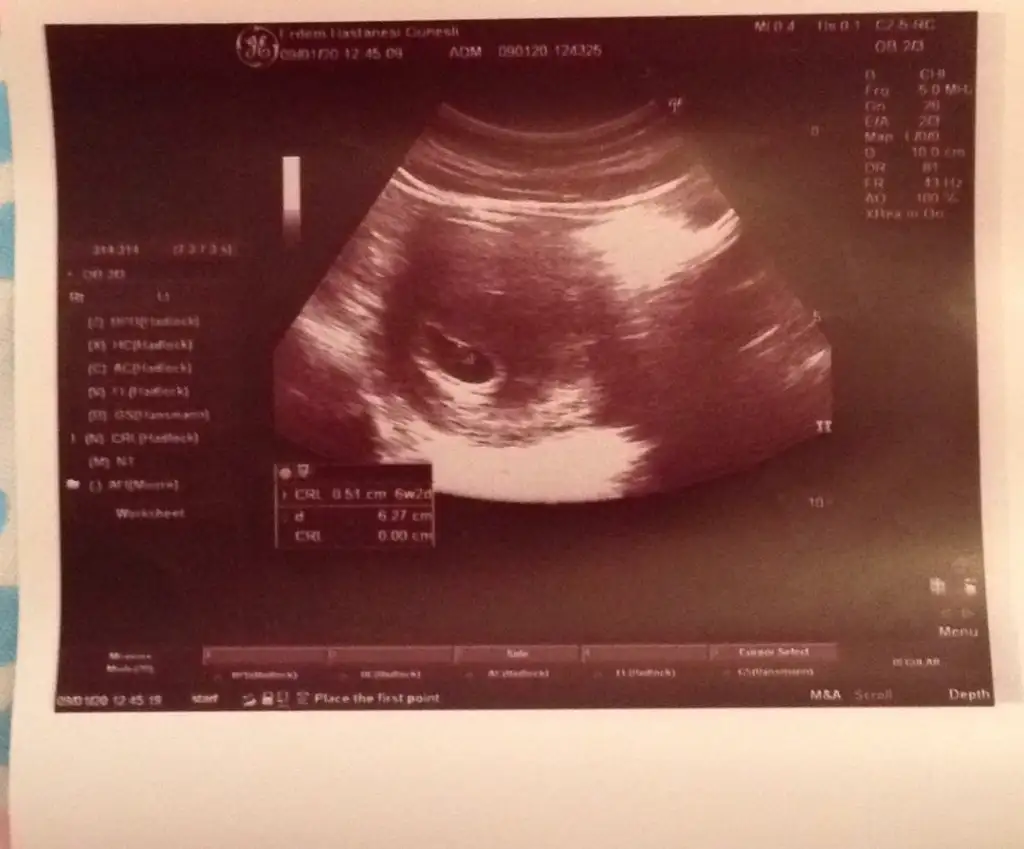

Merhaba benim 6+6 ama ultrasyonda 7+1 cıktı karnımdan bakıldı yorumlayabilirmisiniz acaba